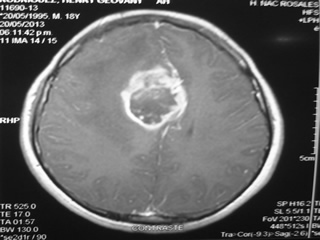

Enfermedades del Cerebro

Dentro de las enfermedades del cerebro mas comunmente vistas en nuestra consulta se encuentran: dolor de cabeza, traumatismo de craneo, neuralgias, aneurismas, malformaciones arteriovenosas, tumores cerebrales, tumores de hipofisis, accidentes cerebro vasculares.